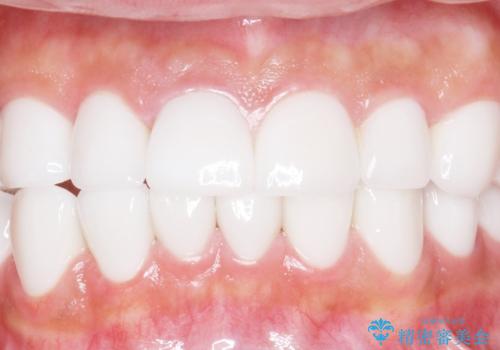

憧れの芸能人のような白い歯に 30代男性

- 憧れの芸能人(ヴィジュアル系バンドマン)のような歯になりたいとのご希望で来院された患者様です。

咬み合わせが悪く矯正も検討されていたそうですが、歯を真っ白にしたいというご希望もあり、28本のすべての歯をセラミックにしたいとのことでした。

虫歯をしっかりと治療したのち、オールセラミッククラウンによる補綴治療を行いました。

憧れのヴィジュアル系バンドマンのような白い歯になり、喜んで下さいました。

不適なレジン充填によるデコボコがなくなったことで歯磨きしやすくなり、また気にされていた咬み合わせも良くなり、ご満足頂けました。

クラウンの種類:オールセラミッククラウン スタンダード

シェード:NW0